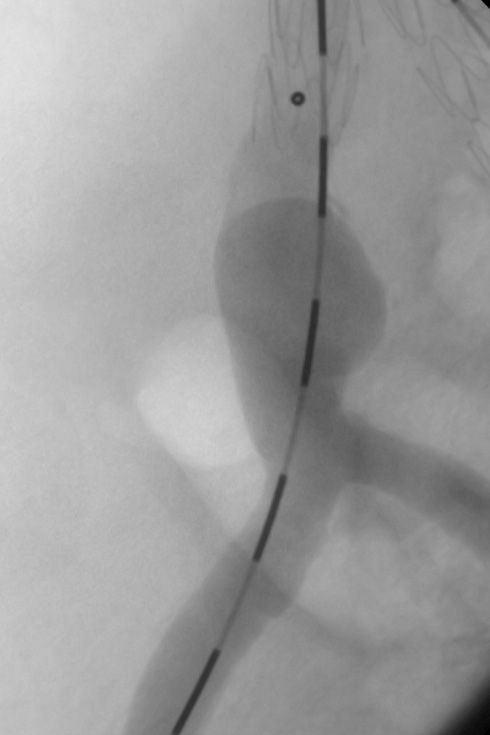

Symedrix has developed the WiTRAC® pre-shaped and scaled guide wire specifically designed to improve AAA procedures.

The AAA wire has three independent zones of stiffness providing optimal support. The ultra-stiff proximal portion of the wire facilitates easy advancing of introducer sheath. The super-stiff distal portion adapts perfectly to the anatomy in the abdominal aortic area and provides sufficient guidance and support for the AAA introducer system. The scaling provides additional support during endovascular procedures. The Tip allows atraumatic positioning in Aorta, thereby protecting the Vessels during the implantation of the stent grafts.

The WiTRAC® AAA guide wire is compatible with a wide variety of anatomies and AAA devices.